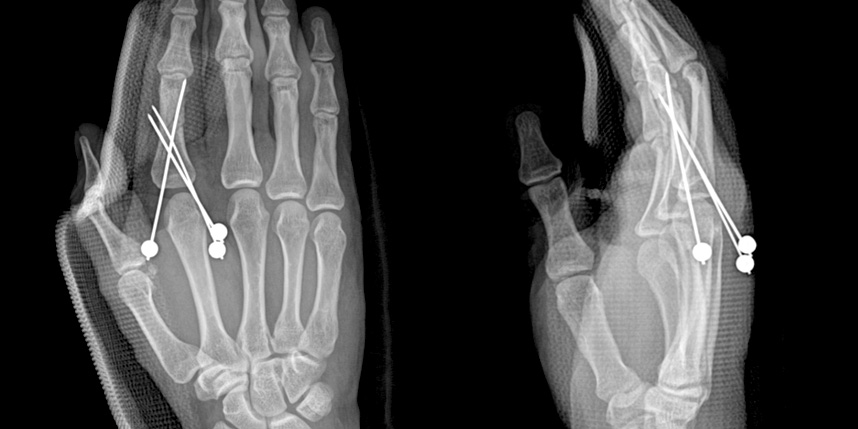

손가락 골절